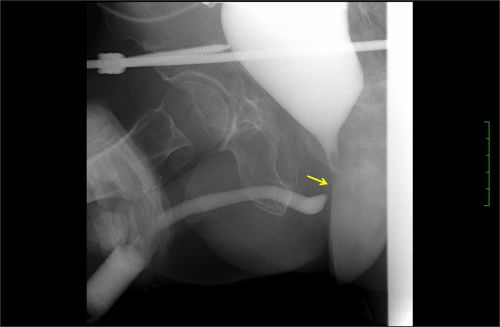

膀胱尿道造影x线检查发现后尿道闭锁的部位和长度。

入院后,经过膀胱尿道造影X线检查发现后尿道闭锁的部位和长度,了解了患者尿道损伤部位没有假道、瘘管发生;骨盆和膀胱尿道三维CT成像显示膀胱尿道的立体结构、与直肠的关系,以及骨盆的稳定性和骨折的恢复情况。